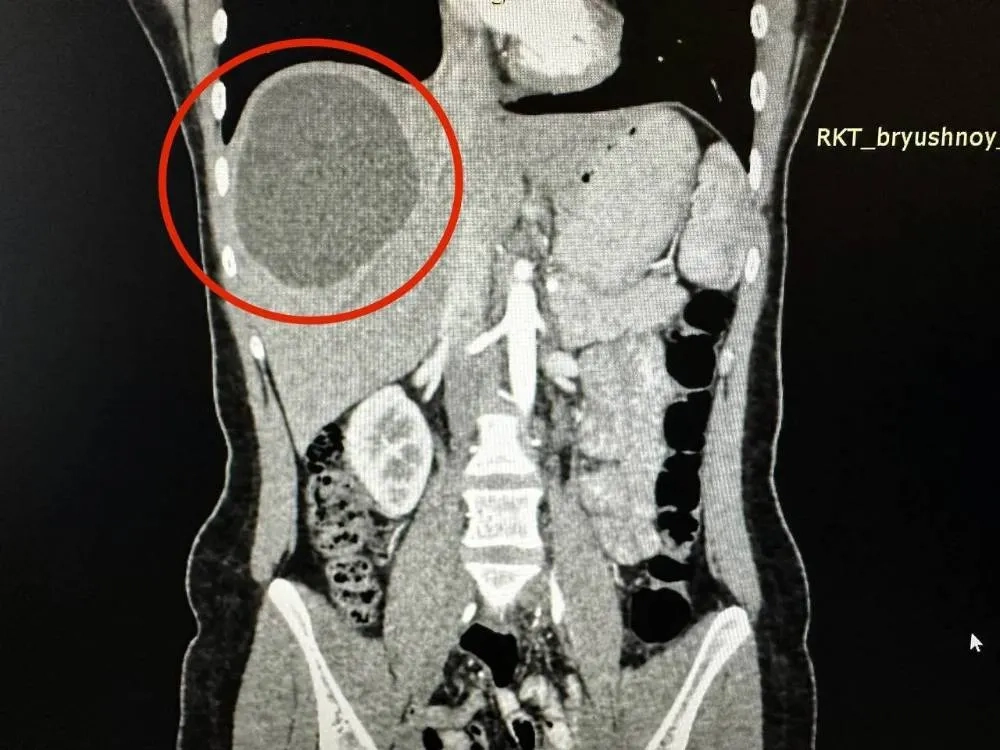

Киста в печени жительницы Казани. Обложка © VK / РКБ Татарстана

По информации сотрудников больницы, девушка обратилась за помощью из-за сильных болей в животе. Специалисты обследовали пациентку, обнаружив в её печени ком червей-паразитов, образовавших кисту 20 на 15 см.

"Медики назначили девушке лечение лекарственными препаратами, чтобы убить паразитов. А через три месяца пациентка легла на операцию в отделение хирургии № 2 РКБ. Черви поразили здоровые ткани печени, поэтому хирургам пришлось убрать практически 1/3 органа", — говорится в сообщении.